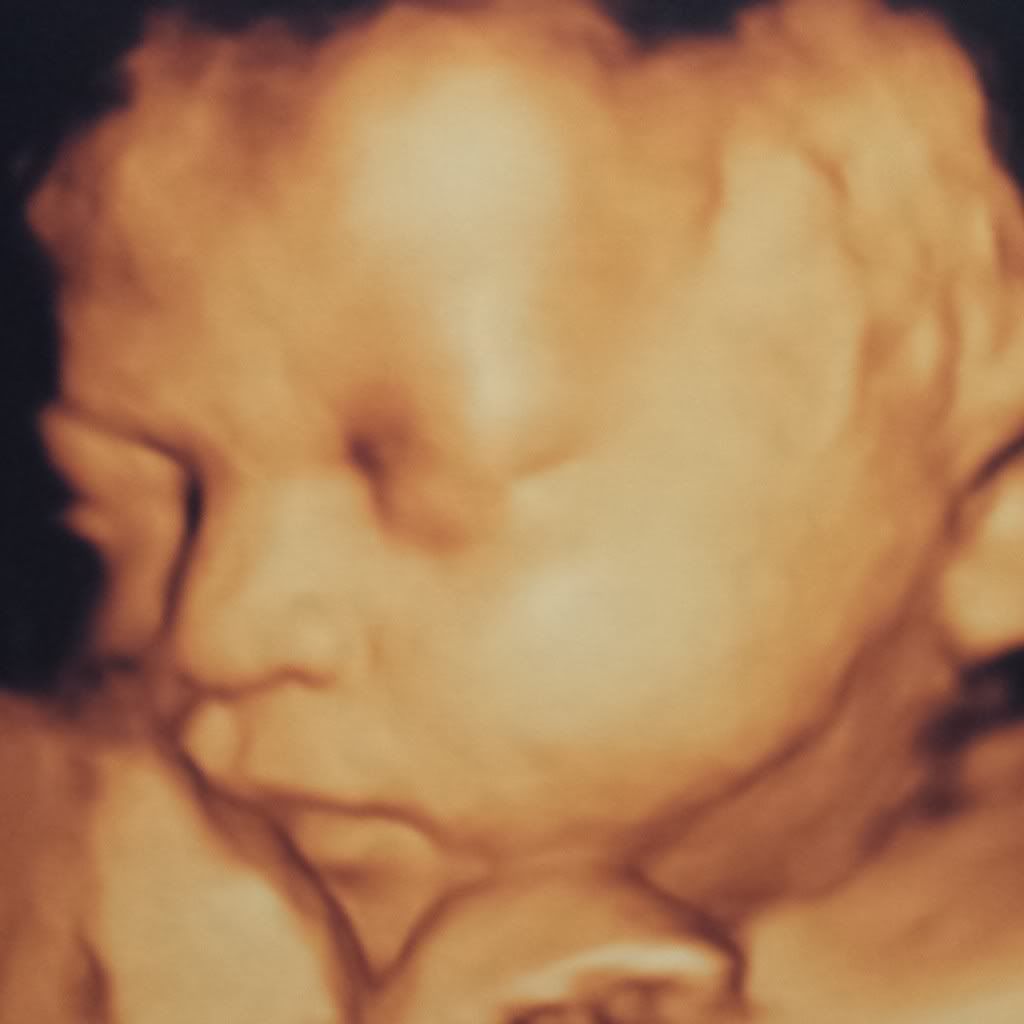

What a cutie! Those 4d pics are amazing. And wow, I'm sorry about your husband. That must be so stressful, I can't even imagine! Thank God he's going to be ok.

@perly everybody has been saying that lol. Thats bc both my girls look like their dad :x thank u

@excitedforoctober thank u girl, she made a whole bunch of face expressions. I just want to squeeze her lol. Her eyes opened for us, stuck out her tongue, she pointed, & smiled. Feel so blessed. Made me feel good seeing her